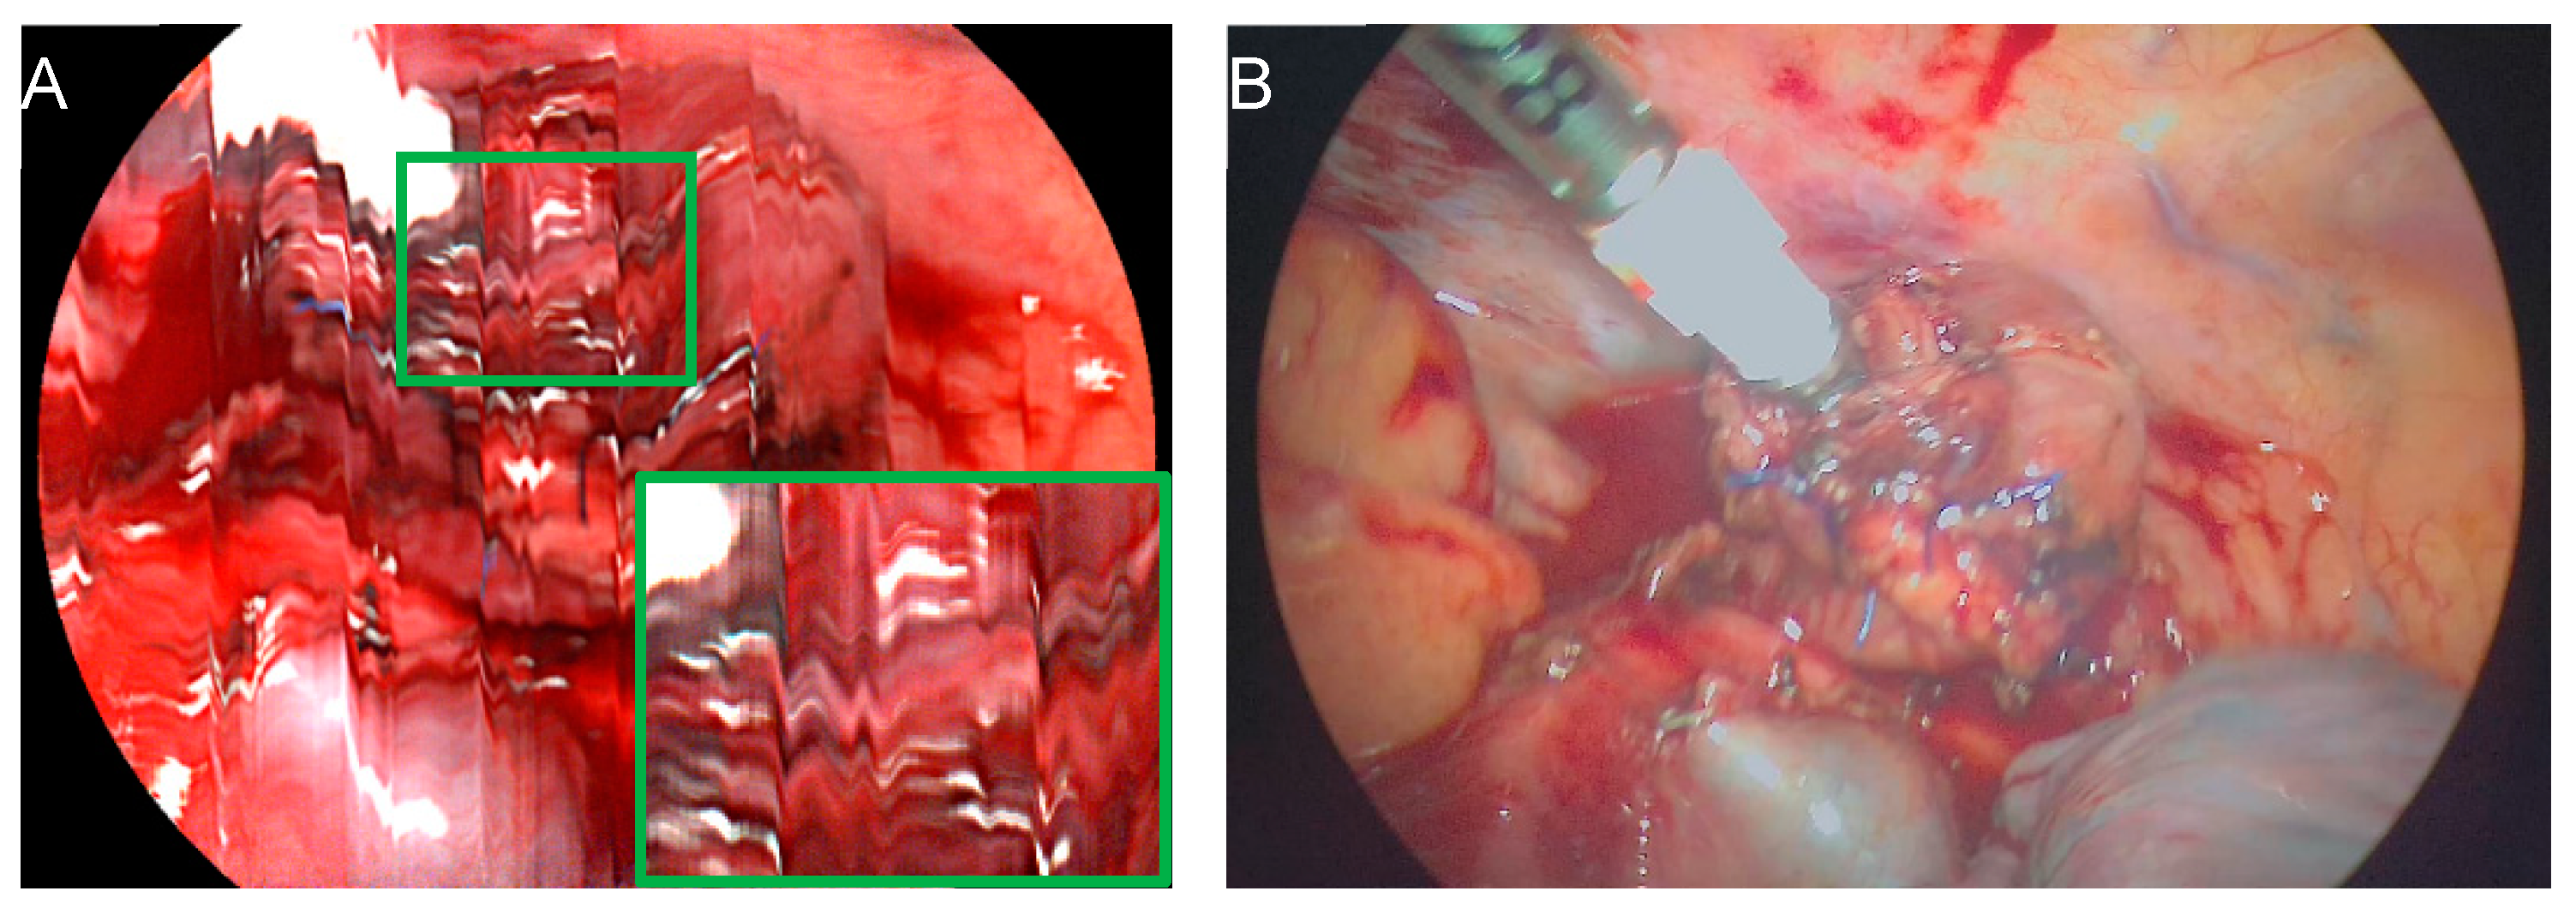

2.2. Surgical Procedure and Hyperspectral Imaging

- Thomaßen, M.T.; Köhler, H.; Pfahl, A.; Stelzner, S.; Mehdorn, M.; Thieme, R.; Jansen-Winkeln, B.; Gockel, I.; Chalopin, C.; Moulla, Y. In vivo evaluation of a hyperspectral imaging system for minimally invasive surgery (HSI-MIS). Surg. Endosc. 2023, 37, 3691–3700. [Google Scholar] [CrossRef] [PubMed]